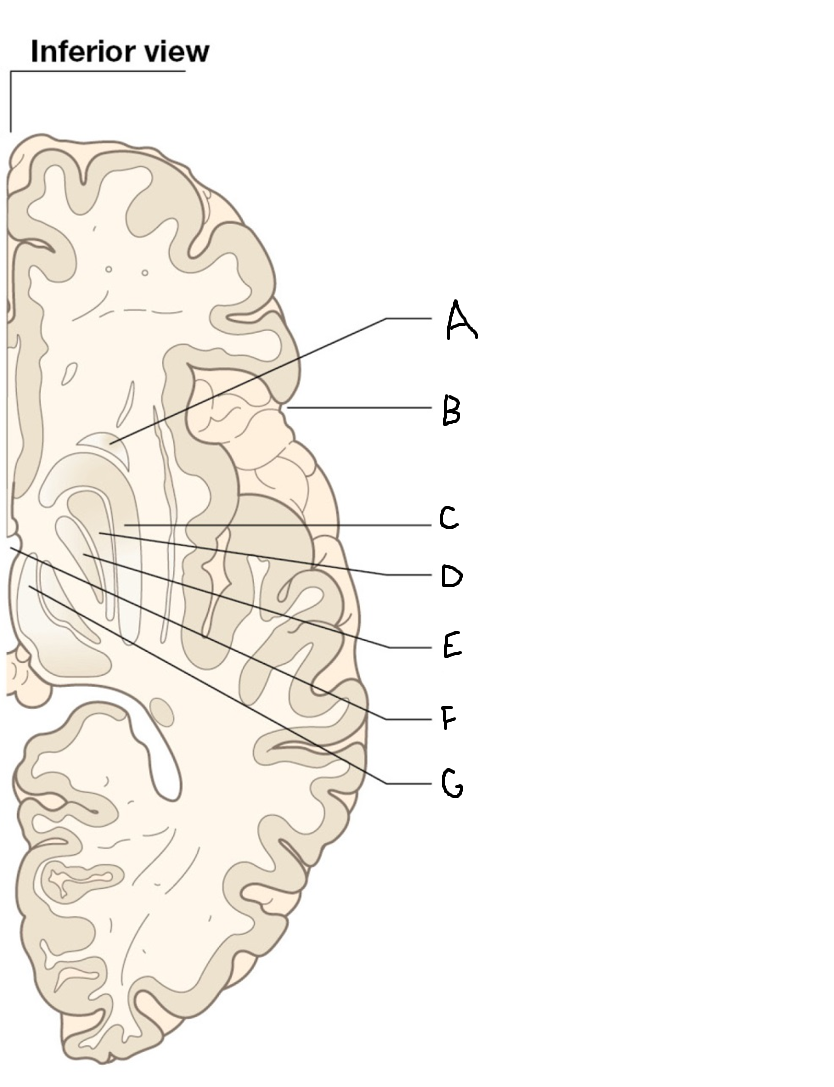

A

internal capsule (anterior limb)

B

caudate nucleus body

C

caudate nucleus head

D

putamen

E

caudate nucleus tail

F

thalamus

G

internal capsule (posterior limb)